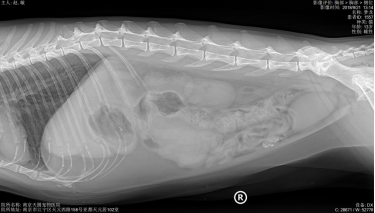

X光显示肺纹理增粗,其他未见异常。